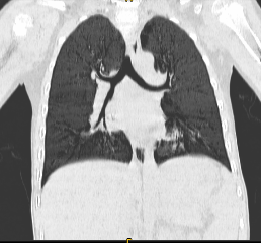

CT三维重建一最小密度投影(minIP)显示气道、支气管异物。